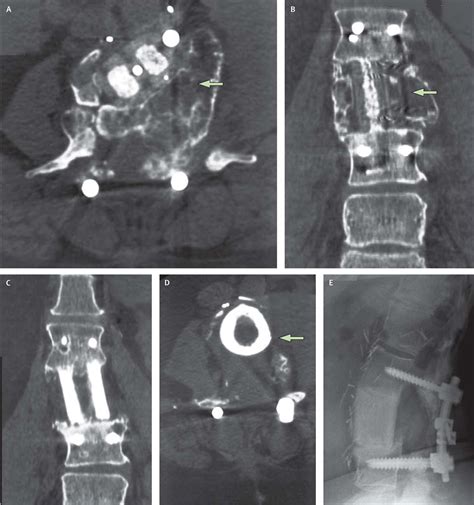

A spinal cord neoplasm is an abnormal growth of cells within or adjacent to the spinal cord. These growths can be classified based on their location: intramedullary (inside the spinal cord substance), extramedullary-intradural (inside the covering of the spinal cord but outside the cord itself), or extradural (outside the spinal cord covering, usually involving the vertebrae). Regardless of the location, these masses exert pressure on the delicate nerve fibers, leading to the clinical manifestations patients experience.

Once a physician suspects a spinal cord neoplasm based on the described symptoms, they will utilize advanced imaging to confirm the diagnosis. The goal is to identify the size, exact location, and potential nature of the growth. Magnetic Resonance Imaging (MRI) is the gold standard for evaluating spinal cord tumors because it provides high-resolution images of the spinal cord, nerve roots, and surrounding tissues.

In some cases, your medical team may suggest a contrast-enhanced MRI to better visualize how the tumor interacts with the spinal cord tissues. Additionally, if the symptoms are ambiguous, doctors might conduct an electromyography (EMG) or nerve conduction study to rule out other peripheral nerve conditions that mimic Spinal Cord Neoplasm Symptoms.